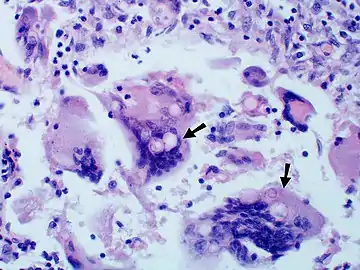

Large yeast-like fungi seen within giant cells at arrows.

Large yeast-like fungi seen within giant cells at arrows. Budding yeasts in cytoplasm of giant cells at arrows. Broad-based budding and double contoured cell wall seen in the giant cell in the center is characteristic of Blastomyces dermatitidis.